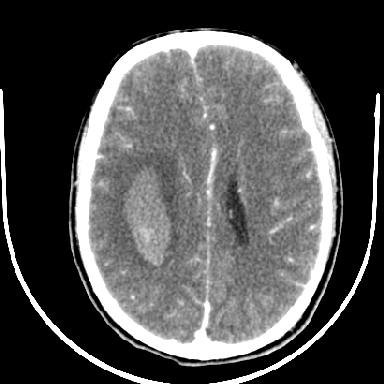

标题: CT6056:脑出血(血管畸形?) [打印本页]

标题: CT6056:脑出血(血管畸形?)

m 40突发头痛左侧偏瘫3小时

考虑高血压性脑出血,依据:

1是高血压性脑出血的好发部位,形态呈肾形,是高血压性脑出血的常见形状

2增强时占位效应加重了,考虑出血还没有停止

3病灶周围水肿不是太厉害,一般肿瘤出血水肿多非常明显

4病灶周围的‘软组织’影没有明显的强化

5至于脑血管畸形引起的出血,暂时没有看到明显的畸形血管影,也不太支持

支持右侧基底节脑出血

右侧基底节区脑出血.

支持右侧基底节区(主要为外囊区)原发性脑出血。

另附部分资料:“血液溢出血管外形成血肿,其内含有大量血红蛋白、血浆白蛋白,球蛋白,因这些蛋白对x线的吸收系数高于脑质,故ct呈现高密度阴影,ct值达40~90h,最初高密度灶呈非均匀一致性,中心密度更高,新鲜出血灶边缘不清。基底节区血肿多为“肾”型,内侧凹陷,外侧膨隆,因外侧裂阻力较小,故向外凸,其它部位血肿多呈尖圆形或不规则形”

术中抽出40ml陈旧血液,血肿底部似见一条索血管影